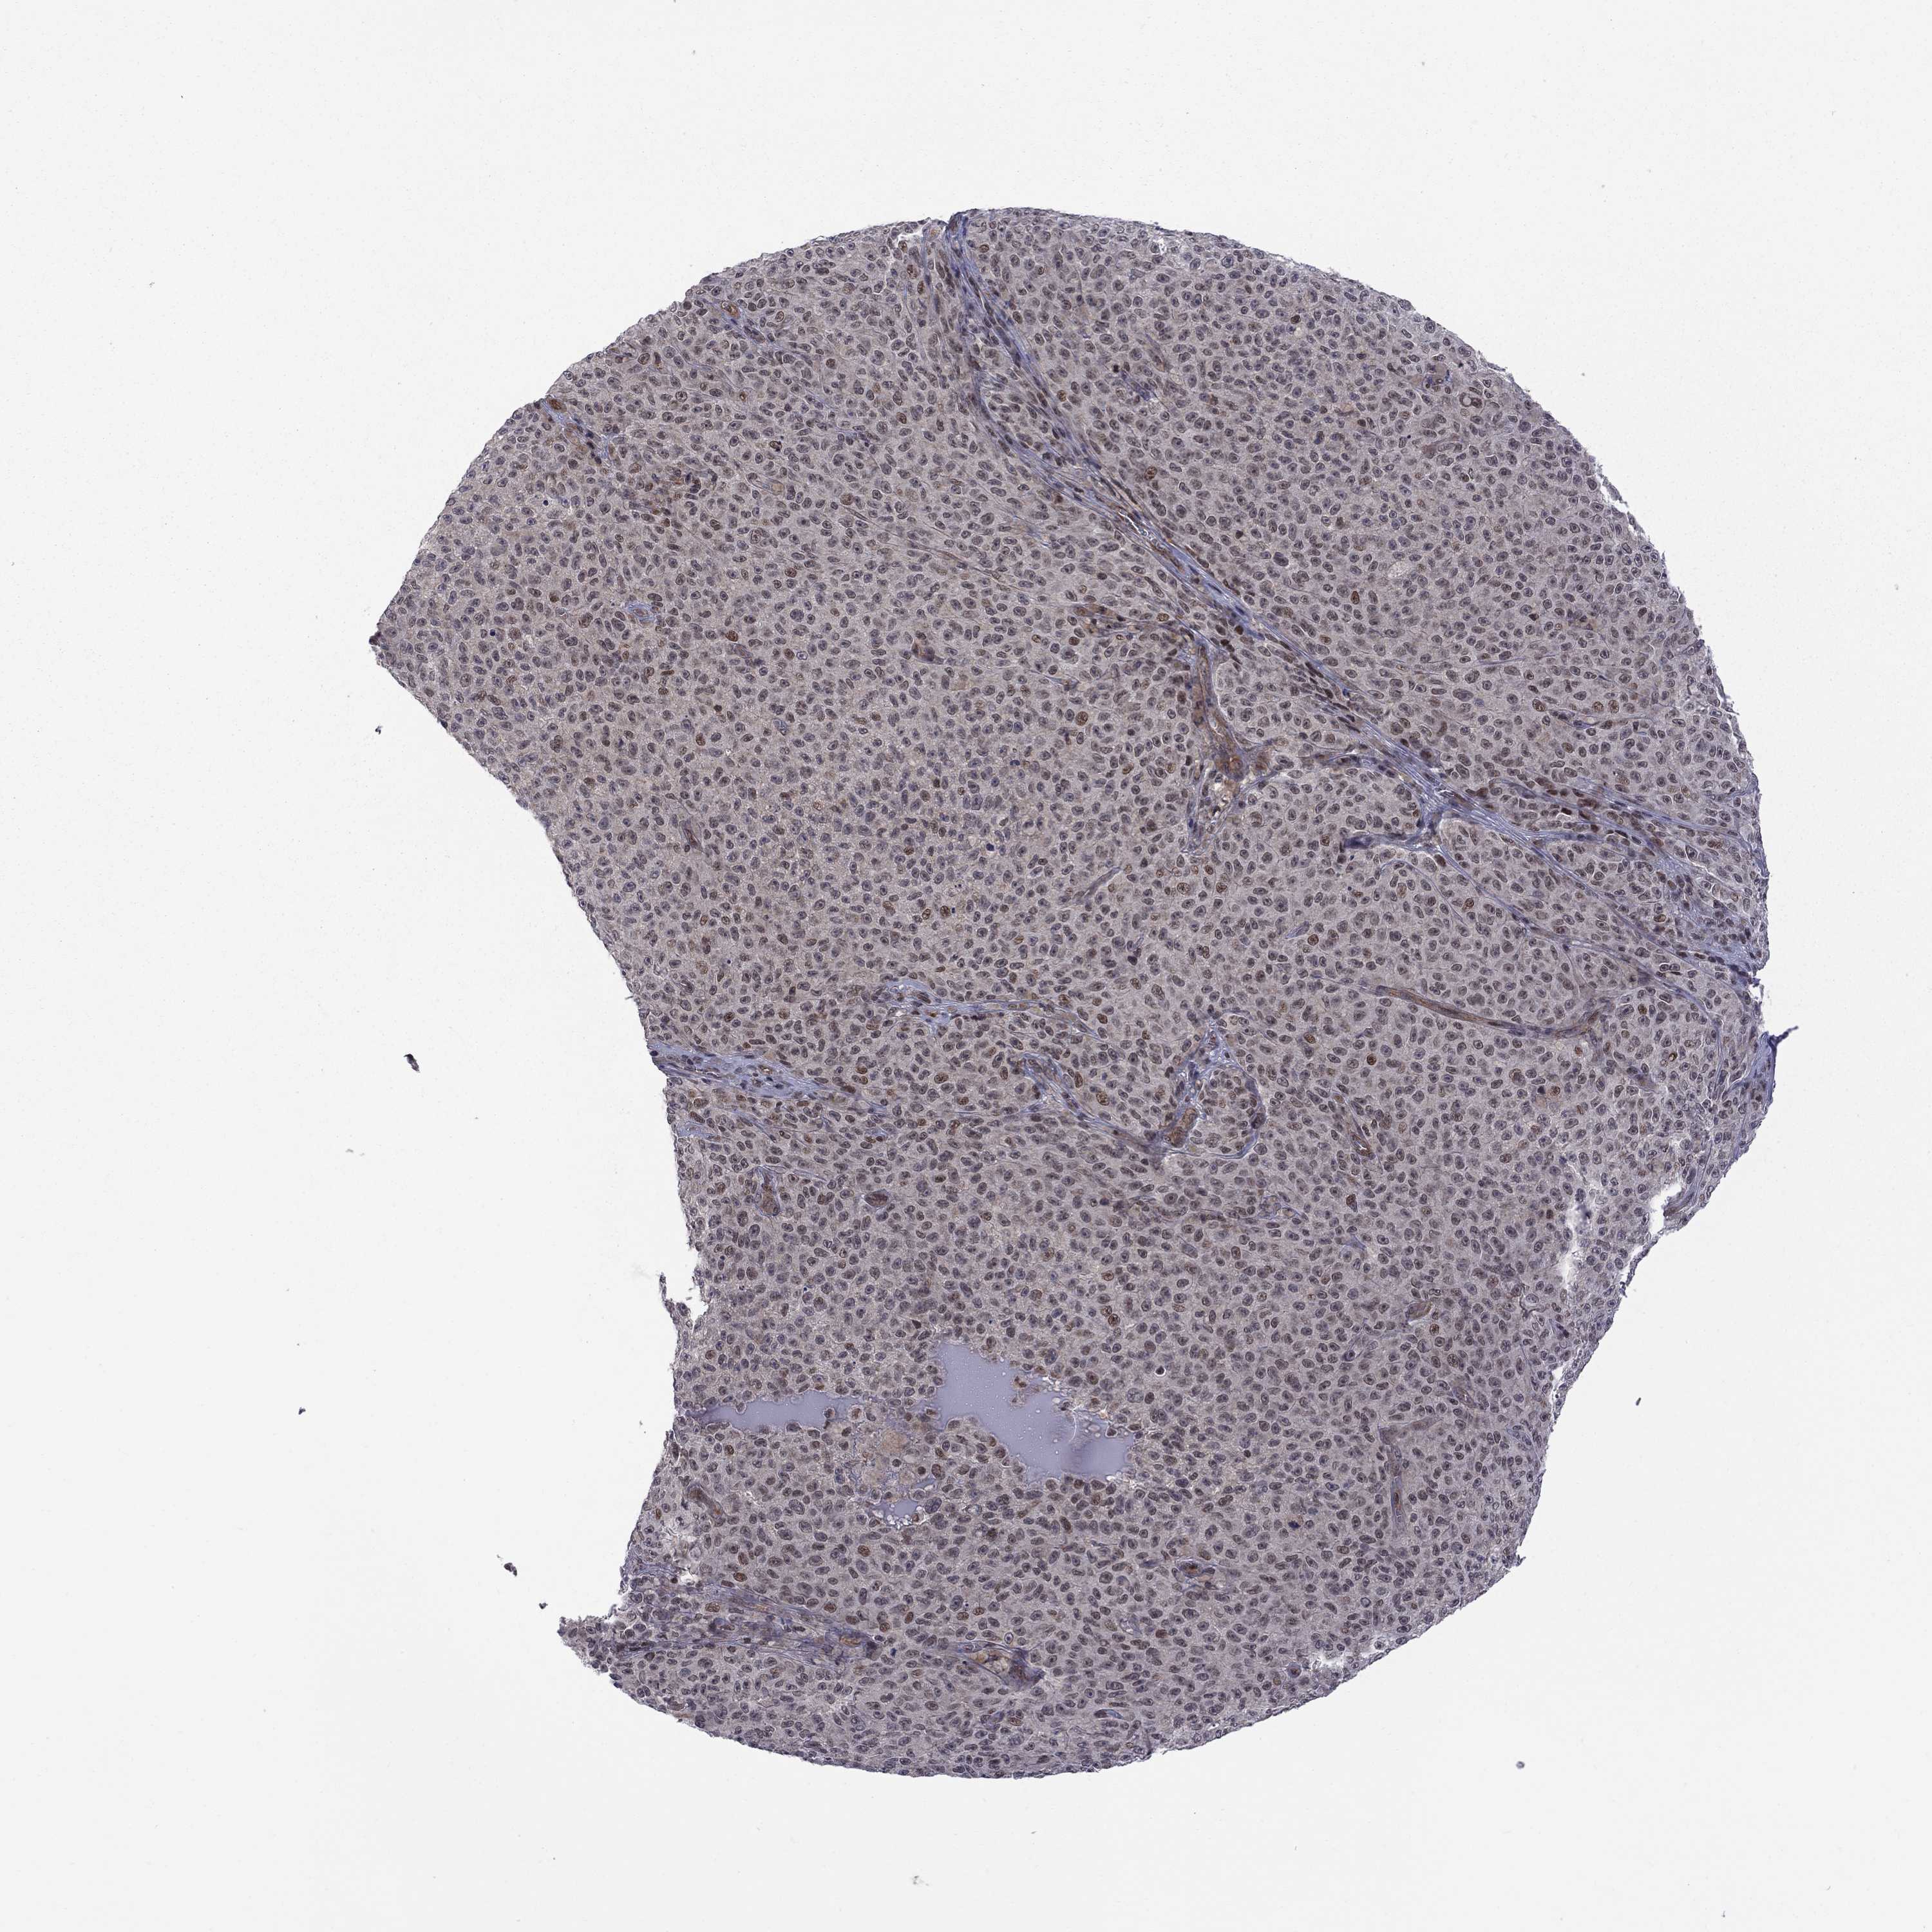

MELANOMA - Protein expressioni

A mouse-over function shows sample information and annotation data. Click on an image to view it in a full screen mode. Samples can be filtered based on level of antibody staining by selecting one or several of the following categories: high, medium, low and not detected. The assay and annotation is described here.

Note that samples used for immunohistochemistry by the Human Protein Atlas do not correspond to samples in the TCGA dataset.

Antibody stainingi

Antibody staining in the annotated cell types in the current human tissue is reported as not detected, low, medium, or high, based on conventional immunohistochemistry profiling in selected tissues. This score is based on the combination of the staining intensity and fraction of stained cells.

Each image is clickable and will lead to virtual microscopy that enables deeper exploration of all samples and also displays staining intensity scores, fraction scores and subcellular localization as well as patient and tissue information for each sample.

Antibody HPA074990

Staining

High

Medium

Low

Not detected

Intensity

Strong

Moderate

Weak

Negative

Quantity

>75%

75%-25%

<25%

None

Location

Nuclear

Cytoplasmic/membranous

Cytoplasmic/membranous,nuclear

Malignant melanoma, NOS

Malignant melanoma, Metastatic site